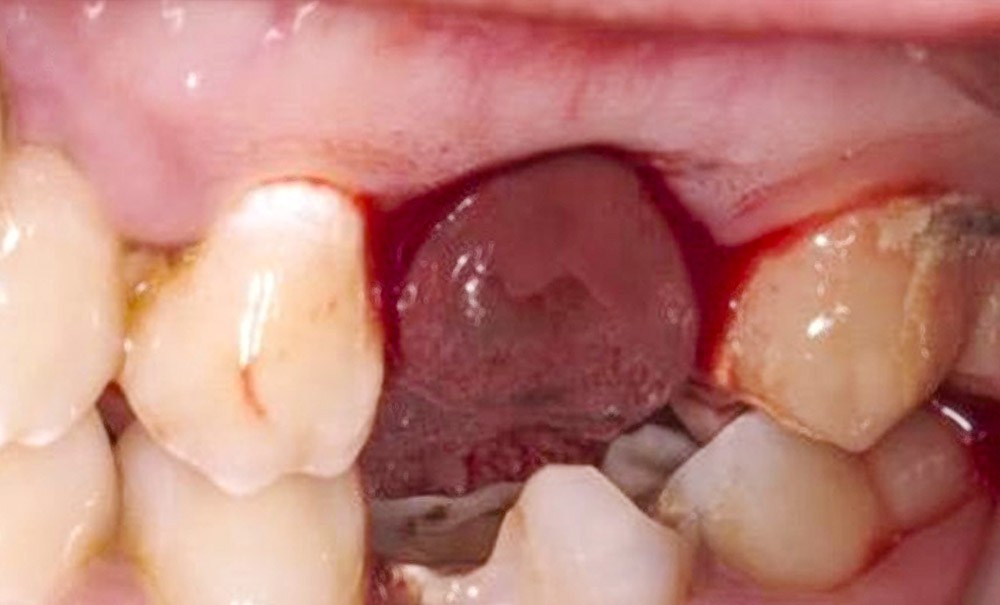

Le premier temps opératoire a consisté à préparer le site receveur. Pour cela, l’avulsion de la 26 a été réalisée trois semaines avant de réaliser l’autotransplantation proprement dite, de manière à pouvoir bénéficier d’un site receveur osseux hypervascularisé en pleine cicatrisation.

Lors du deuxième temps opératoire dédié à l’autotransplantation, un curetage léger de l’alvéole en cours de cicatrisation a été réalisé, suivi de l’essayage de la réplique du transplant (fig. 2). Après…